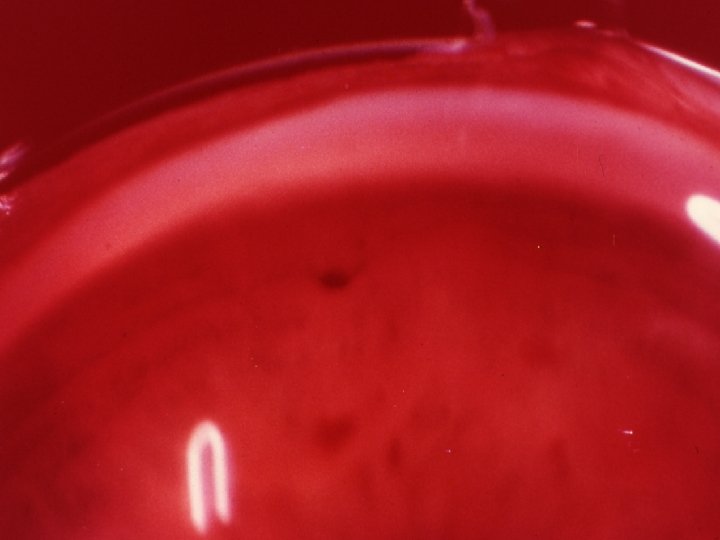

Traumatologie et Brûlures oculaires 2 - Contusions du globe Le syndrôme traumatique du S. postérieur Hémorragies rétiniennes Intra ou pré-rétiniennes: BAV , graves si touchent la région maculaire Intravitréenne: Pluie de suie, BAV brutale